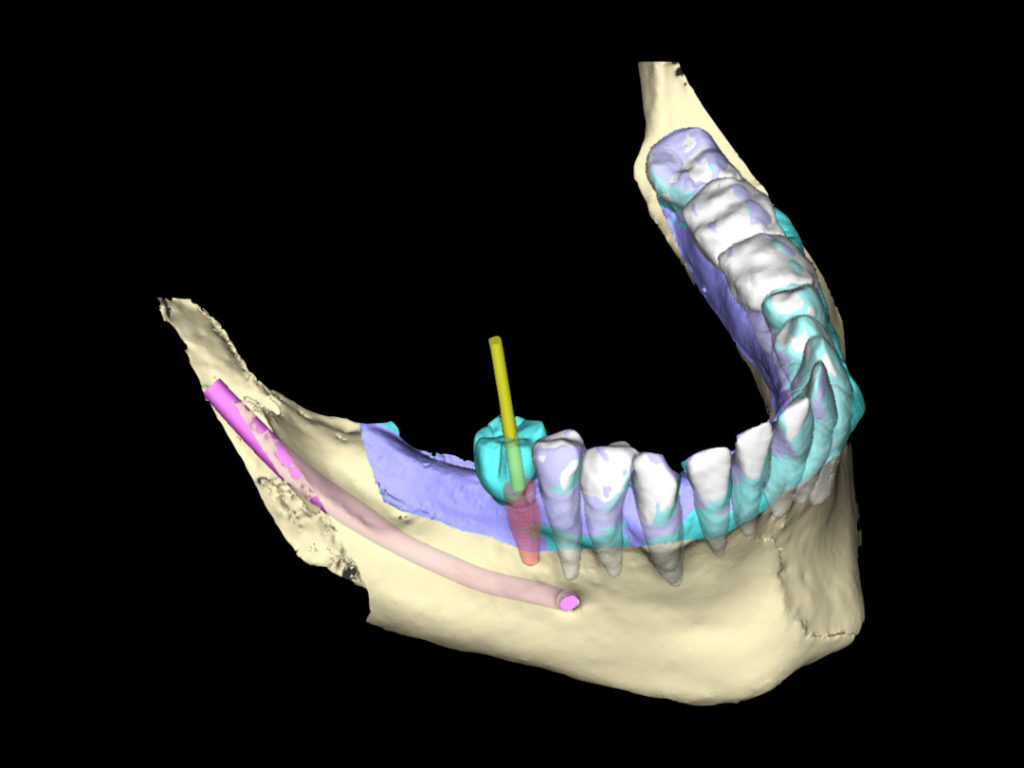

Eine vorrausschauende und präzise Planung in der Implantologie ist der Schlüssel, um für die anschließende Prothetik ein planbares und erfolgreiches Ergebnis zu erzielen.

Wir nutzen 3D-navigierte Planungsprogramme

• CoDiagnostiX

• Exoplan

Durch die Vielzahl an Möglichkeiten, die diese Programme bieten, stellen wir vollnavigierte Bohr- und Pilotbohrschablonen sowie einfache OP-Schablonen her.

Unser breites Portfolio reicht von der Einzelzahnversorgung bis hin zu All-on-X-Fällen. Unsere hohe Kompetenz in der Implantatprothetik basiert auf unserer langjährigen Erfahrung und unserem erprobten Vier-Augen-Prinzip. Unser komplexes Wissen nutzen wir im Austausch mit Ihnen gern, um Ihnen unterschiedliche Lösungen vorzustellen oder gemeinsam über einen Fall zu diskutieren. Denn unser Ziel ist es immer, das bestmögliche Ergebnis für Ihre PatientInnen umzusetzen.